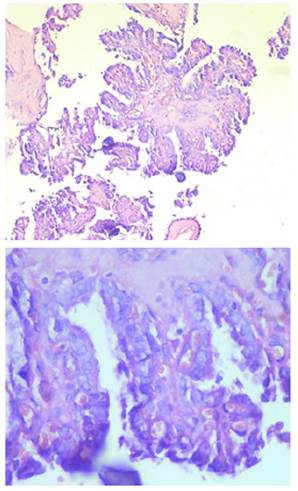

Se trasladó la paciente al área de recuperación. La biopsia definitiva reportó: microcarcinoma papilar (Figura 15), tamaño tumoral de 0,25cm, sin compromiso de la cápsula, concluyendo diagnóstico de: carcinoma diferenciado de tiroides (microcarcinoma papilar), de bajo riesgo por MACIS (Metástasis, Edad, Completa resección, Invasión y Tamaño) y ATA (Asociación Americana de Tiroides), estadio I (Comisión Conjunta Estadounidense sobre el Cáncer) 10.

Figura 15: Corte histológico de la pieza anatómica, donde se observa: contorno nuclear irregular, pseudoinclusiones nucleares y el aspecto claro y vidrioso en el núcleo de las células foliculares en el carcinoma papilar de la glándula tiroides.

Figura 23: Corte histológico de la pieza anatómica, donde se observan características de adenoma paratiroideo: células principales de núcleo redondo y citoplasma granular pequeño.